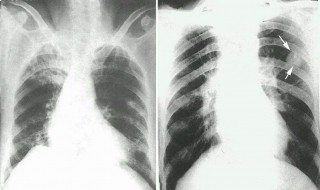

大部分的肺结核病人,百分之九十八肺结核病人,只要坚持了正规的治疗,运用正规的化疗方案,坚持到国家规定的全程治疗,短程督导治疗,能够把整个疗程做足,百分之九十八的患者是可以治愈的,所以说肺结核病人完全没有担心能活多久的问题,因为它是一种可以治愈的疾病。